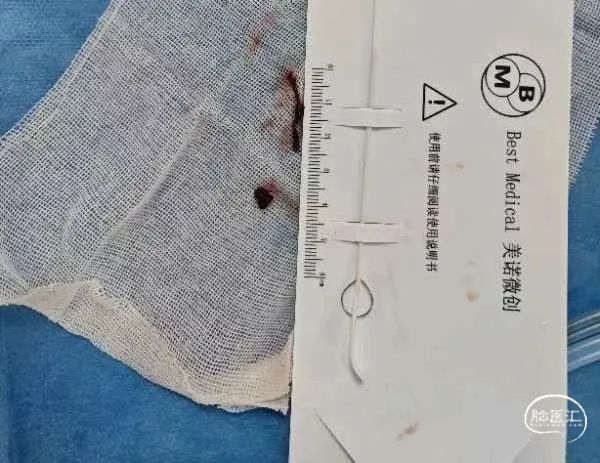

5F 125cm Tethys AS®血栓抽吸导管外接50ml注射器负压抽吸,关闭所有滴注,ADAPT技术,抽吸出黑色血栓成分,冒烟见血管再通,造影显示左侧颈内动脉、大脑中动脉、大脑前动脉及其分支显影好,前向血流TICI分级3级。

⾎管内介⼊治疗是颅内外大脑中动脉闭塞的标准治疗⽅式,其预后与再通时间、复流程度密切相关。精准的病变部位及性质的识别可减少不必要的检查,争取更短的开通时间。本案例为大脑中动脉分叉处混合血栓的取栓治疗,混合血栓具有一定韧性,且位于大脑中动脉分叉处,如首选支架取栓,取栓支架释放后血栓位置较易移动,无法固定并被支架完全包裹,不易取出,且栓子易反复在上下干之间停摆而无法实现完全再通。术中所使用加奇生物 Tethys AS®血栓抽吸导管,相较Tethys推送更加顺畅,到位更加优秀,一次取通,配合加奇生物 DCwire®微导丝 ,精准超选,节省手术时间,临床预后令人满意。